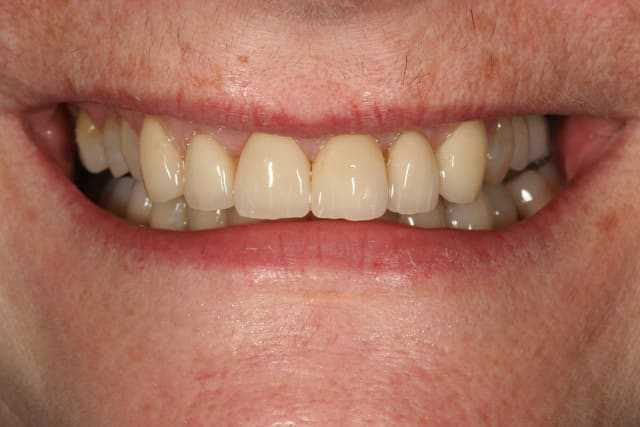

voilà le resultat collé

je suis resté trop supragingival, mais la patiente est très contente (ouf, c'est l'essentiel !)

elle a sa gouttière pour la nuit

Sourire w9qjjh - Eugenol